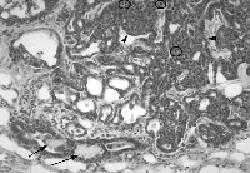

The Mouse Tumor Biology Database encourages researchers to submit their own pathology images such as the one below showing mammary adenocarcinoma in a JAX® Mice model of mammary cancer.

Solid and tubular mammary adenocarcinoma. Relatively normal mammary gland ducts containing pink proteinaceous material (arrows) approach cells forming tubular structures of various sizes lined by darkly basophilic, small cuboidal cells. Near the top of this image, these cells fill the tubular structures (arrowheads) forming solid areas. Mitotic figures (circles) are common in the more cellular areas (tumor is from strain FVB/N-Tg(WapNotch4)10Rnc/J).